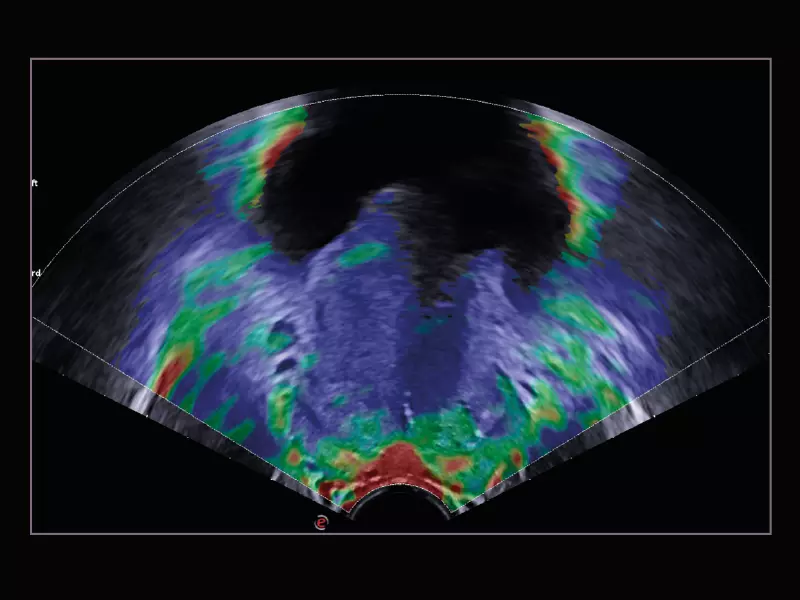

MyLab™9 Platform - Prostate contrast enhanced imaging (CnTI™)

MyLab™9 Platform - Prostate contrast enhanced imaging (CnTI™)